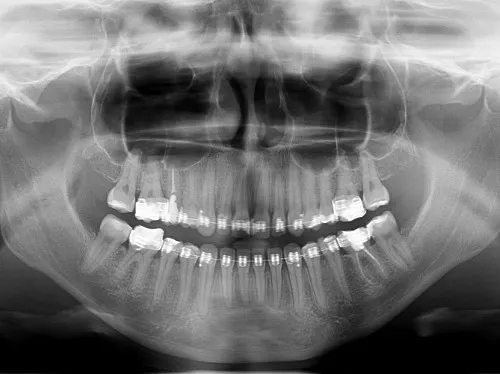

Rola zdjęcia RTG: co stomatolog widzi na pantogramie?

Podstawowym narzędziem diagnostycznym, które pozwala mi zidentyfikować torbiel, jest zdjęcie rentgenowskie (RTG). Wykonujemy zarówno zdjęcia pantomograficzne, które dają przegląd całej szczęki i żuchwy, jak i zdjęcia punktowe, precyzyjnie obrazujące konkretny ząb i jego okolice. Na zdjęciu RTG torbiel jest widoczna jako wyraźne, okrągłe lub owalne przejaśnienie w strukturze kości, często z wyraźnymi, gładkimi granicami. To właśnie dzięki RTG możemy wykryć wiele bezobjawowych torbieli, które w innym przypadku pozostałyby niezauważone.